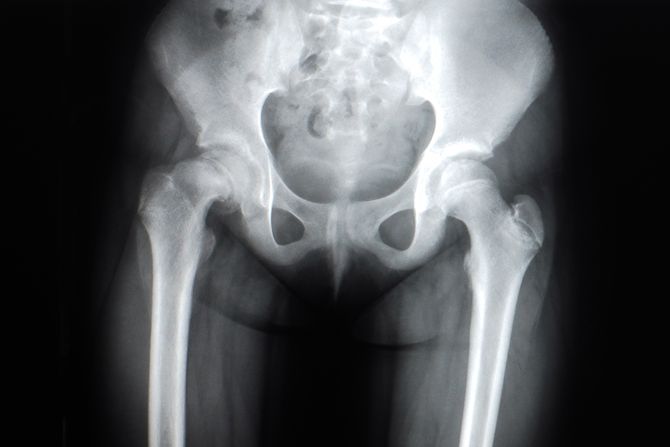

Naloženo je rendgensko snimanje, jer su lekari sumnjali na prelom ili iščašenje kuka, što može izazvati bol u kolenu.

Ispostavilo se da muškarac, koji je u prošlosti imao alkoholnu anamnezu, pati od izuzetno retkog poremećaja - okoštavanja polnog organa.

Ovakvo stanje nastaje kada se soli kalcijuma nagomilavaju u mekom tkivu penisa i stvaraju ekstraskeletnu kost.

Reč je o pojavi koja je dokumentovana u stručnoj literaturi svega 40 puta kroz istoriju. Muškarac nije pokazao druge simptome tipične za stanje, poput otoka.